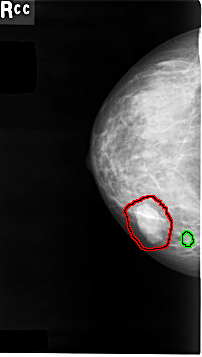

C_0008_1.RIGHT_CC

RIGHT_CC LINES 4640 PIXELS_PER_LINE 2624 BITS_PER_PIXEL 12 RESOLUTION 50 OVERLAY

FILE: C_0008_1.RIGHT_CC.OVERLAY

TOTAL_ABNORMALITIES 2

ABNORMALITY 1

LESION_TYPE MASS SHAPE LOBULATED MARGINS MICROLOBULATED

ASSESSMENT 4

SUBTLETY 5

PATHOLOGY MALIGNANT

ABNORMALITY 2

LESION_TYPE CALCIFICATION TYPE PUNCTATE DISTRIBUTION CLUSTERED

PATHOLOGY BENIGN